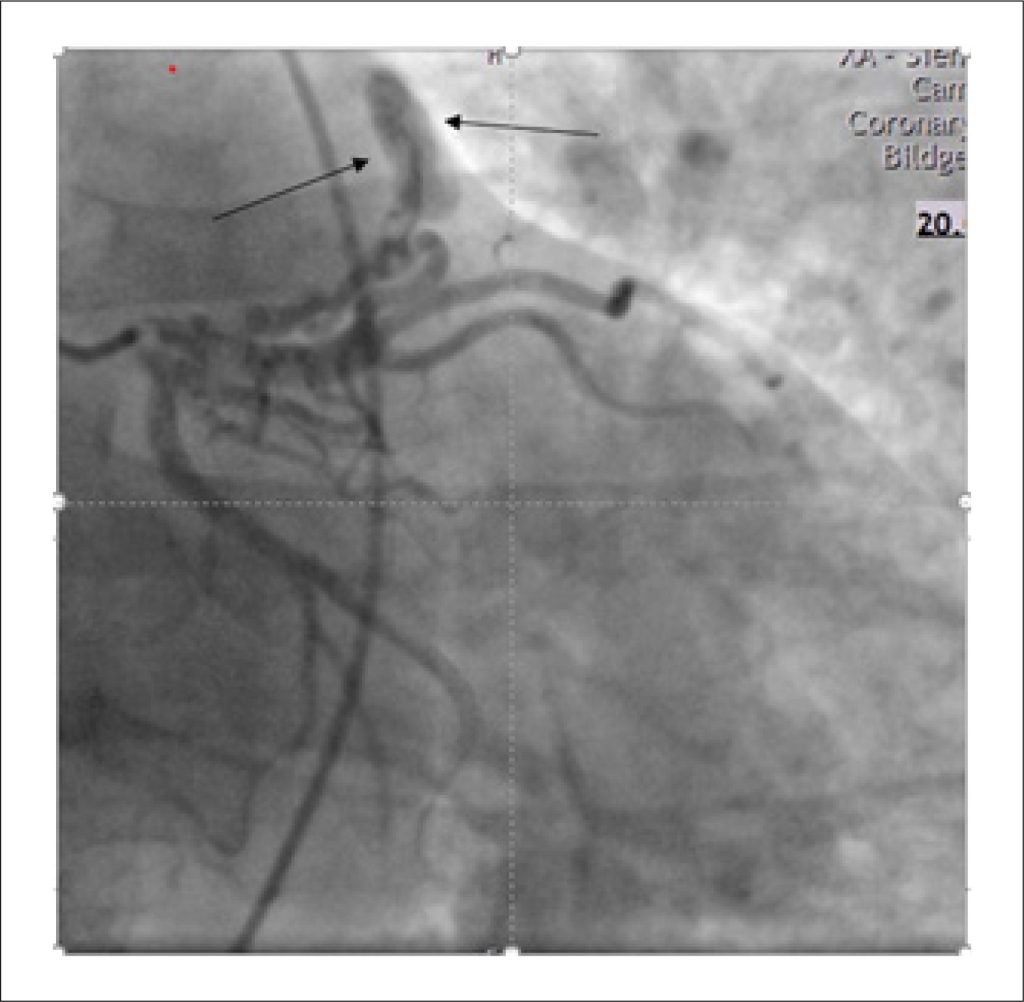

Coexistence of Partial Anomalous Pulmonary Venous Connection and Coronary Artery Fistulas: A Rare Case Report

We present the case of a 55-year-old man who experienced an acute onset of dyspnoea lasting approximately two hours. Initial clinical assessment and routine investigations—including physical examination, echocardiography, electrocardiography, and right and left heart catheterization—raised suspicion of an underlying cardiac abnormality, prompting further evaluation. Subsequent cardiac Magnetic Resonance Imaging (MRI) and Multi-Detector Computed Tomography (MDCT) revealed the presence of a Partial Anomalous Pulmonary Venous Connection (PAPVC) accompanied by Coronary Artery Fistulas (CAFs). Given the non-complex characteristics of the shunt in this case, a shared decision was reached with the patient to proceed with conservative management.